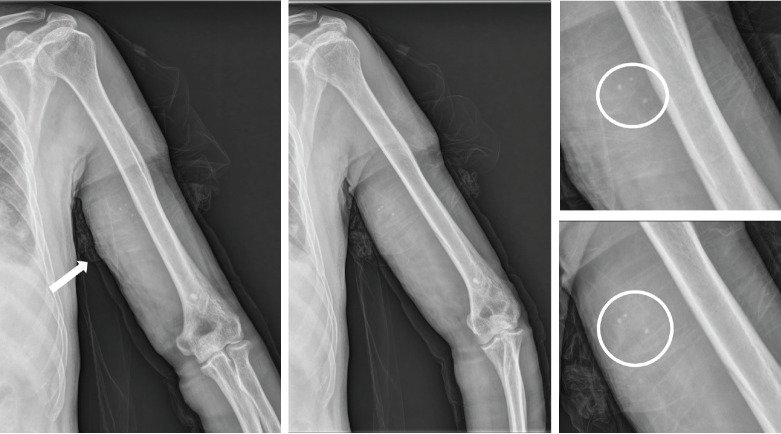

肌肉内血管瘤在肌肉骨骼疼痛鉴别诊断中很少被考虑,特别是在上肢,而且它们与肱二头肌内的感染性脓肿共存是非常罕见的。我们报告一个56岁男性二头肌肌内血管瘤伴脓肿形成的病例,其表现为左上臂疼痛和肿胀,热感,发红,肘关节屈曲和前臂旋后受限。c反应蛋白水平高(25.43 mg/dL),术前左上臂和肘部运动,视觉模拟评分为10分。x线平片示3个小静脉。磁共振成像显示二头肌左侧有一个界限不清的强化病灶(2.5×2.7×9.8 cm),病灶内t1加权信号增强,病灶内有一个小、圆、低信号强度的病灶,与肌内血管瘤一致,二头肌内侧有一个地理上的非强化区域,与感染性肌炎合并脓肿形成一致。我们进行了手术切除肌肉内血管瘤和引流脓肿在二头肌。术后5周,所有功能限制均消除,5个月随访无复发。

Intramuscular hemangiomas are rare in musculoskeletal pain differentials, especially in the upper extremities. We report a case of a 56-year-old male with an intramuscular hemangioma and abscess in the biceps brachii, presenting with pain, swelling, and limited elbow movement. High C-reactive protein (25.43 mg/dL) and visual analog scale score of 10 were noted. Radiograph showed 3 phleboliths. MRI revealed an enhancing lesion (2.5×2.7×9.8 cm) and abscess. We performed surgery for excision of the intramuscular hemangioma and drainage of the abscess in the biceps muscle. By 5 weeks post-surgery, all functional limitations had resolved, and no recurrence was observed at the 5-month follow-up.